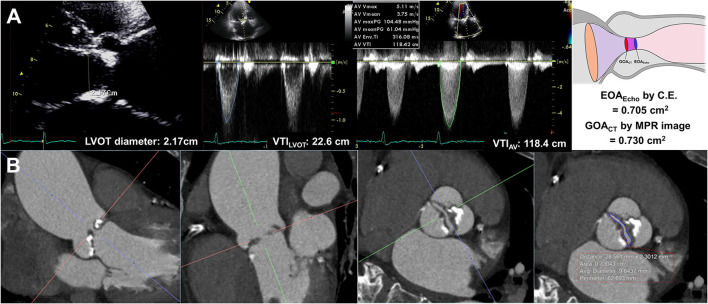

EOAEcho was derived from the continuity equation. The left ventricular outflow tract (LVOT) flow was assessed on the apical three-chamber view. The LVOT diameter was measured during mid-systole 0.5–1 cm below the aortic annulus on the parasternal long-axis view. The velocity–time integral of the LVOT (VTILVOT) was assessed using pulse-wave Doppler. Assuming the circular geometry of the LVOT, the stroke volume was calculated using the following formula: LVOT diameter2 × 0.785 × VTILVOT. The highest peak velocity across the AV, mean pressure gradient (MPG), and velocity-time integral of the AV (TVIAV) were measured from multiple windows using continuous-wave Doppler (Figure 1). All measurements represent an average of three cardiac cycles for patients with sinus rhythm and an average of five cardiac cycles for patients with atrial fibrillation. The severity of AS and combined aortic regurgitation (AR) was assessed based on the current guidelines (15, 16).

Figure 1.

Effective orifice area by continuity equation (A) and geometric orifice area by multiplanar computed tomography image (B).

Cardiac CT measurements

All CT scans were performed with a dual-source CT scanner (SOMATOM Definition Flash; Siemens Healthcare, Forchheim, Germany). Before CT angiography, a non-enhanced prospective ECG-gated scan was performed to measure aortic valve calcium score with standardized calcium scan parameters (slice collimation of 0.6 mm, slice width of 3.0 mm, tube voltage of 120 kV, and a tube current of 50 mAs). CT angiography was performed in retrospective ECG-gated data acquisition mode using the triple-phase injection method (70 ml of iopamidol followed by 30 ml of 30% blended iopamidol with saline and 20 ml of saline at 5 ml/s). Images were generated using iterative reconstruction (sinogram-affirmed iterative reconstruction). Image reconstruction was performed with a medium kernel (I36f), and the reconstruction slice thickness was 0.75 mm with 0.5–mm increments. For all patients, 10 transverse data sets were reconstructed every 10% of the cardiac cycle. Image analysis was performed using 3D software (Aquarius iNtuition, Ver. 4.4.11, TeraRecon, San Mateo, CA, USA). For planimetry, the image volume was rotated into a plane perpendicular to the LVOT and aortic root (20). LVOT imaging involved the orientation of a cross-sectional plane of the LVOT using three orthogonal planes from multiplanar reconstruction at or immediately under the lowest implantation base of the aortic cusp, and two orthogonal diameters (minimal and maximal) were measured (4). GOACT was defined as the CT planimetry-derived AV area. Planimetry of the AV area was performed at the level of the aortic leaflet tips in the mid-systolic phase, which provided the best visualization of the open aortic valve, usually at 20–30% of the R-R interval, regardless of BAV types (Figure 1, Supplementary Figure 1). Planimetry of the LVOT was performed immediately below the AV in the same phase used for the measurement of the AV area. The angle between the LVOT-AV and aorta (°) was measured during the mid-systolic phase. The AV calcium score was measured using commercial software (Aquarius iNtuition, Ver. 4.4.11, TeraRecon, San Mateo, CA, USA). Observers segmented the AV calcium score by carefully including the region of interest in the AV leaflet and annulus and excluding calcium in the adjacent sinus of Valsalva, left ventricular outflow tract, or mitral annulus, and image noise or beam hardening artifact was excluded. From the segmented ROI, the AVC volume was measured, and an AVC score was calculated using the Agatston method (21, 22). All CT analyses were independently performed by two radiologists blinded to clinical information, echocardiographic results, and CT analysis results of the other reader. Intraclass correlation coefficients (ICCs) were calculated to assess the inter- and intra-observer variability of the GOACT. A total of 20 samples were assessed by the same observer on different occasions in random order and were also assessed by another observer.